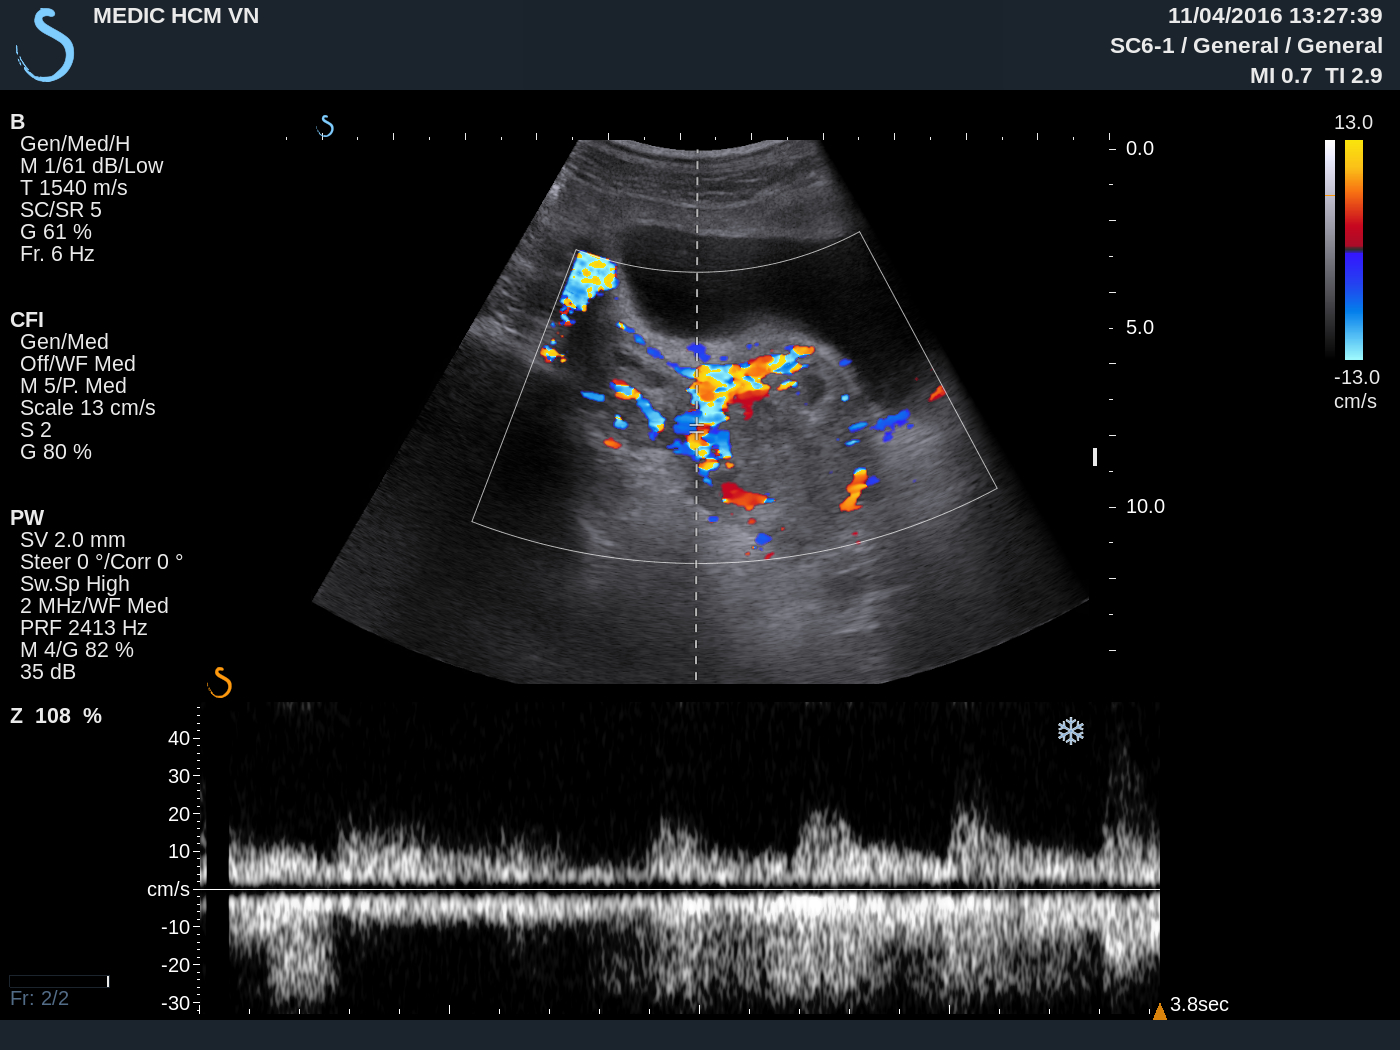

Ultrasound again detected one hypervascular mass at the neck of uterus ( see 3 USimages).

And beta HCG of blood test is high.

MRI uterusof this mass suspected gestation at neck uterus in the scar of cesarian section before.